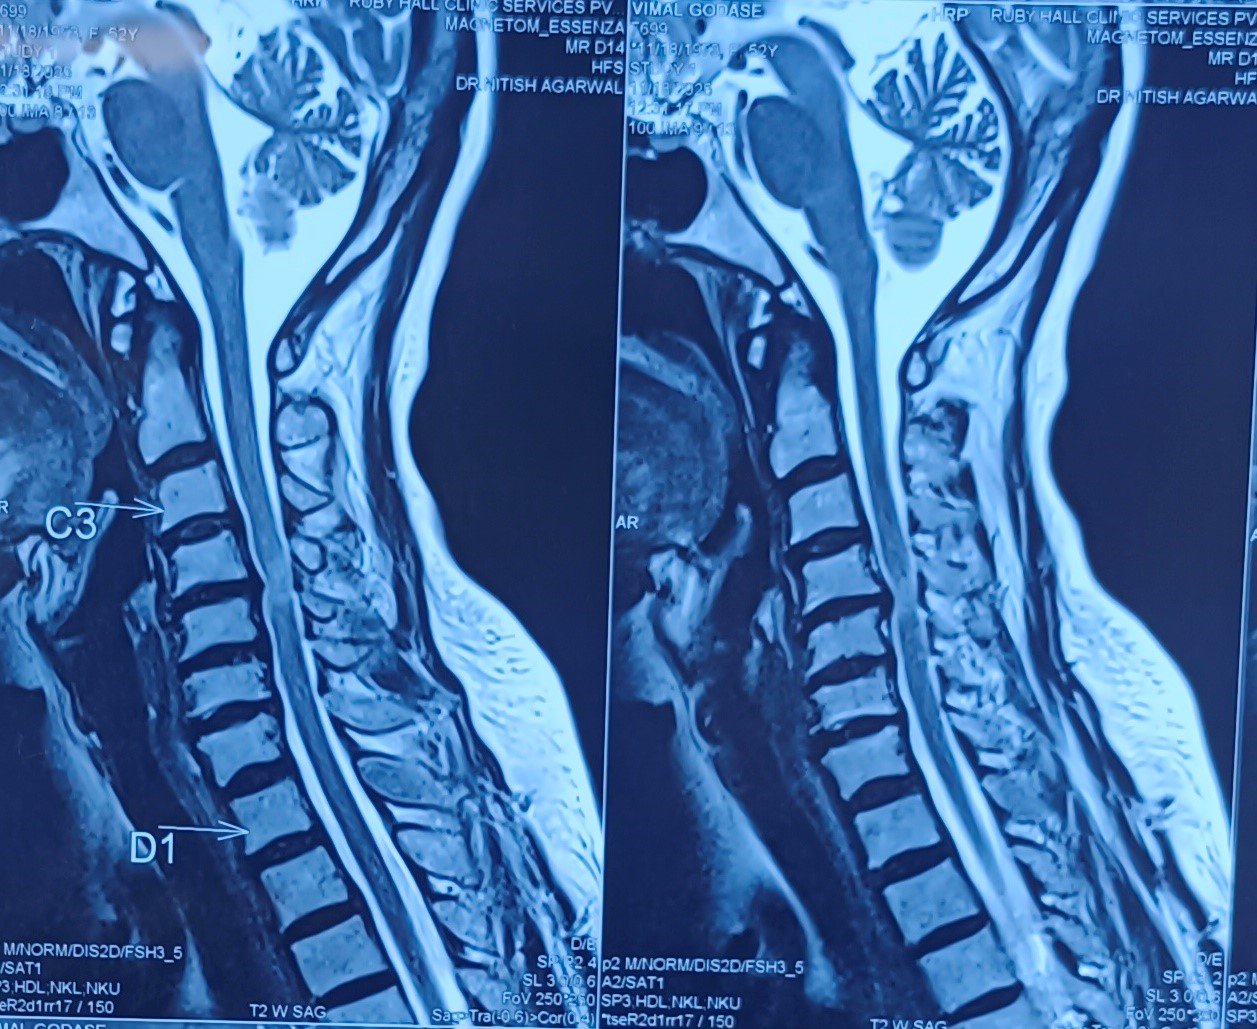

Cervical Disc Prolapse with Spinal Cord Compression

Special Cases Cervical Disc Prolapse with Spinal Cord Compression Condition:Cervical disc prolapse in which the herniated disc compresses the nerve roots and spinal cord, often associated with spinal cord edema. Symptoms:Neck pain, numbness in hands, weakness, difficulty in walking, and coordination problems. Treatment:Anterior Cervical Discectomy and Fusion (ACDF) – The…